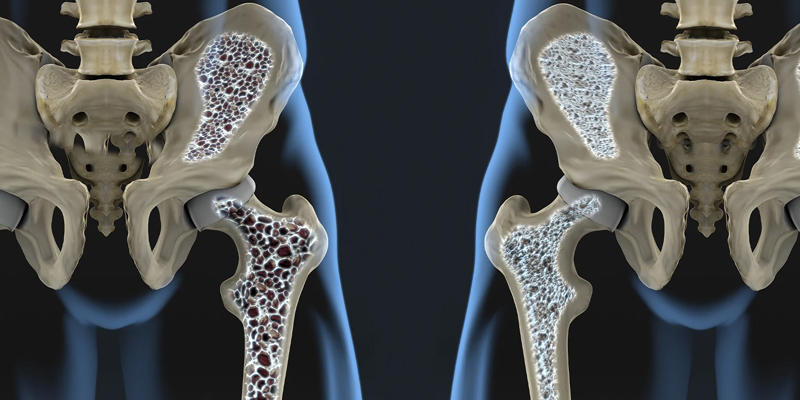

Osteoporosis is a debilitating condition characterized by weak, brittle bones that are highly susceptible to fractures. It occurs when the body loses bone mass faster than it can replace it, leading to a decrease in bone density and strength. Often termed a "silent disease," osteoporosis typically progresses without noticeable symptoms until a fracture occurs, commonly in the hip, spine, or wrist.

- **Advanced Bone Density Testing (DXA)**: Utilizing dual-energy X-ray absorptiometry (DXA) scans for accurate measurement of bone density and assessment of fracture risk, allowing for early detection.